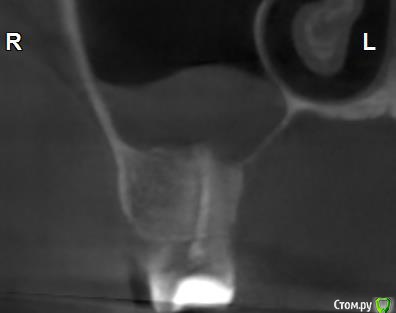

Здравствуйте! Верхний правый шестой зуб пломбировали 3 месяца назад. Примерно месяц назад он начал ныть, после насморка, сначала периодами, а теперь почти постоянно. При постукивание (ощущается не совсем так, как другие зубы) и пальпации десны он не болит. 2,5 месяца назад удаляли кисту из гайморовой пазухи. Может ли быть это какое-то воспаление и есть ли вероятность устранить его какими-нибудь антибиотиками, если да, то как, или может удалить зуб? Если есть воспаление, то какие могут быть последствия если не удалить зуб?

(Снимки с КТ, первые 8(Image) - сделаны сейчас,по 4 в разных проекциях, вторые 8(Before) - сделаны 5 месяцев назад до удаление кисты и повторного пломбирование зуба( до повторного пломбирование он реагировал на горячее, был запломбирован 3 года))